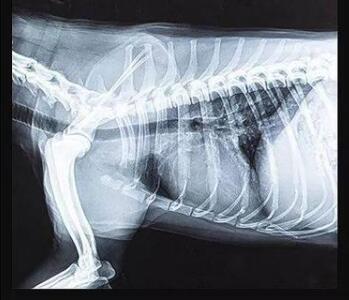

傳統的平板探測器,相當于普通攝像機,對于拍攝急促呼吸狀態下的寵物,成像效果存在著明顯缺陷。而新一代寵物平板探測器,宛如高速攝像機,能夠清晰記錄動物每一個精準瞬間。

寵物dr專用平板拍攝效果